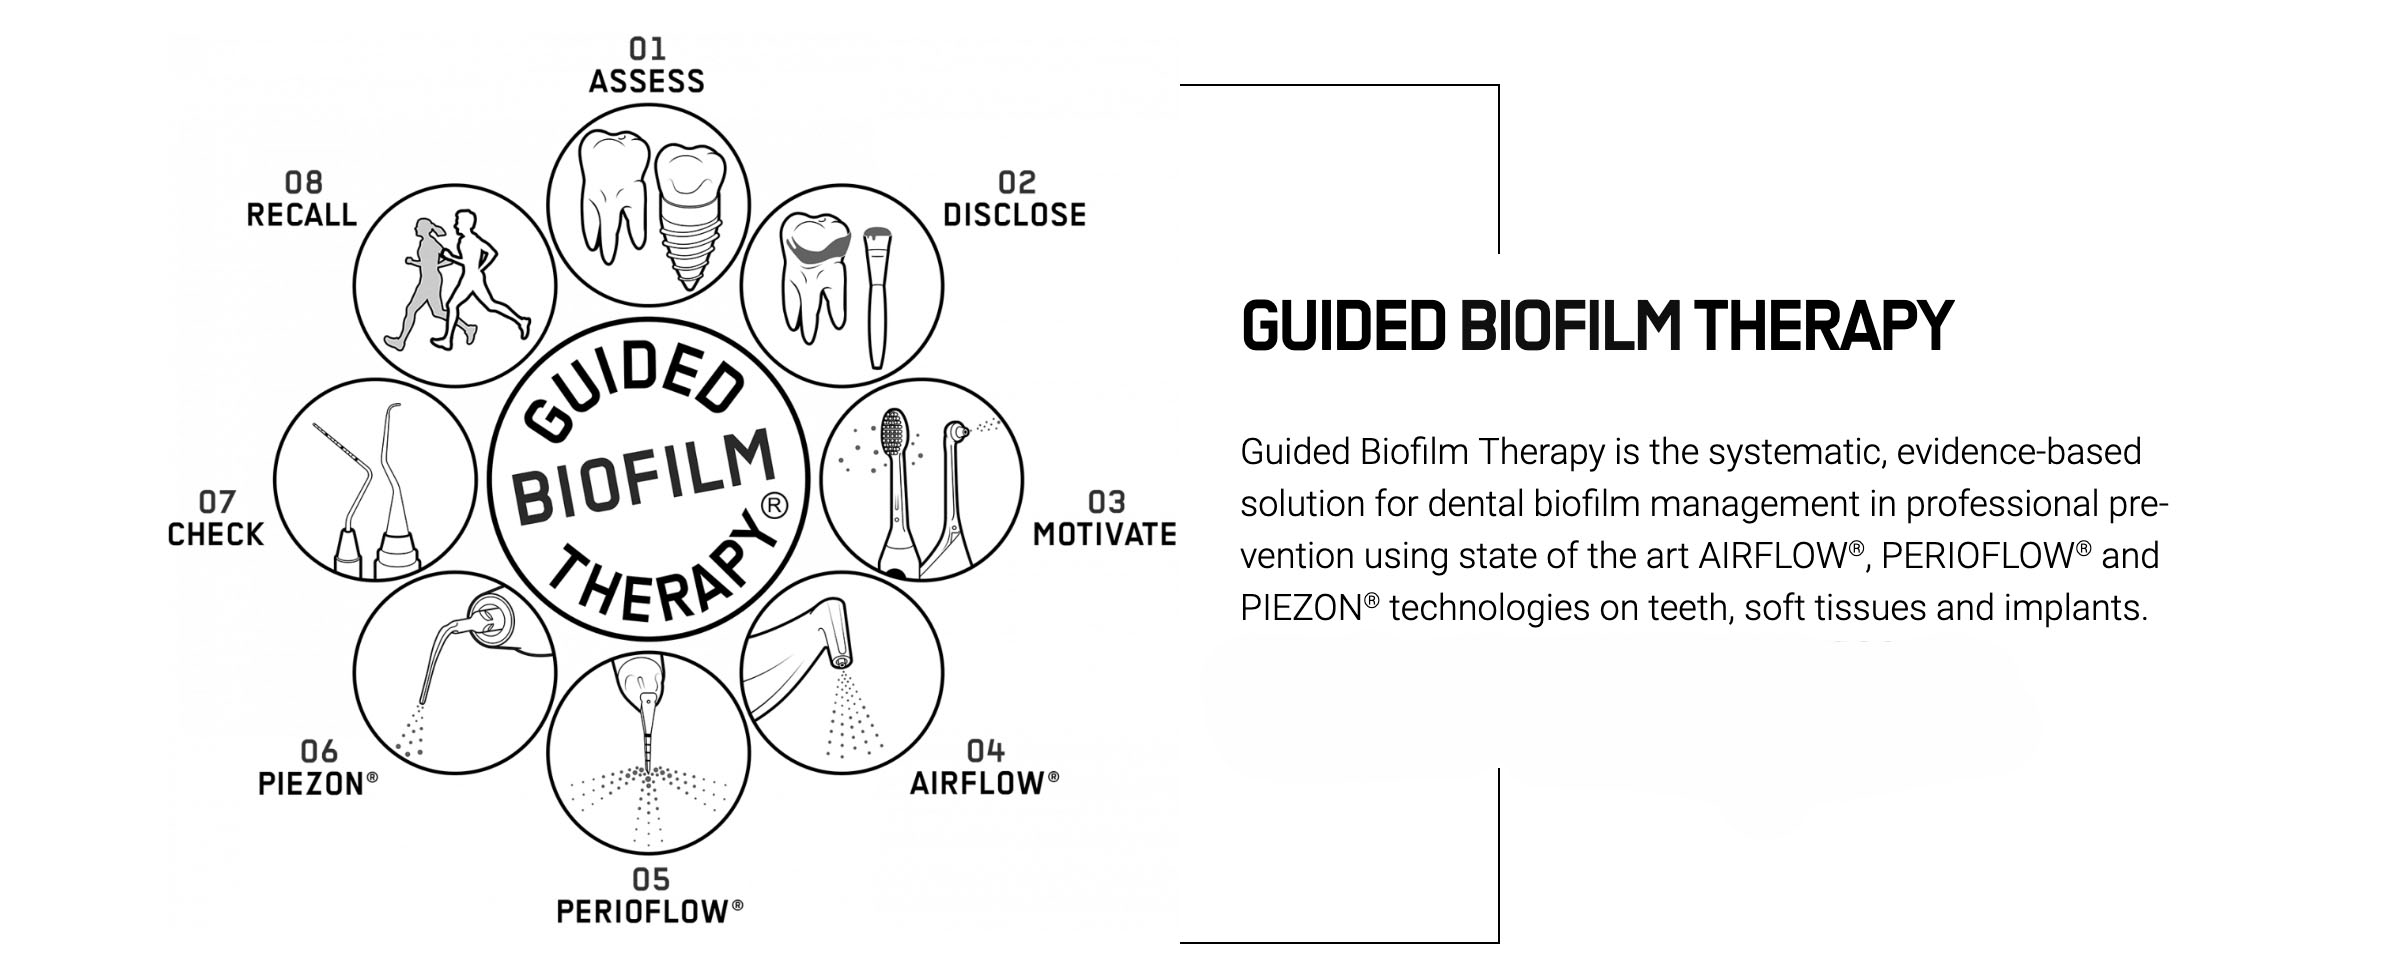

THE 8 STEPS OF THE GBT PROTOCOL:

01 ASSESS

Probe and screen every clinical case:

- Healthy teeth, caries, gingivitis, periodontitis

- Healthy implants, mucositis, peri-implantitis

- Start by rinsing with BacterX Pro mouthwash